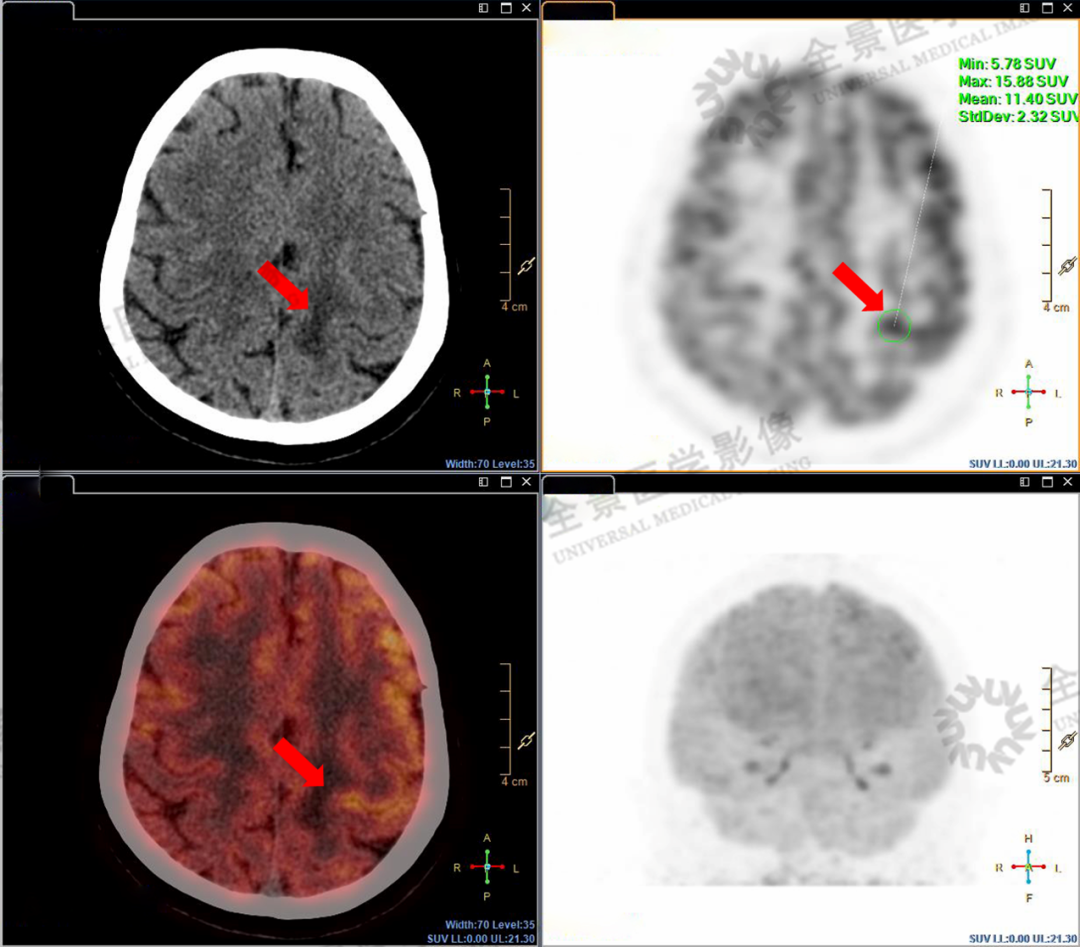

由于大脑皮层活跃时也有正常的代谢增高表现,仅凭PET/CT还不能准确定性脑部高代谢区域的性质,因此又有针对性地做了头颅磁共振扫描。

经过PET/CT和MR检查图像融合分析后确定:左额中回的高摄取区未发现占位,考虑为正常脑实质代谢;额定交界区高代谢结节考虑为转移。

额顶交界区高代谢结节,考虑转移